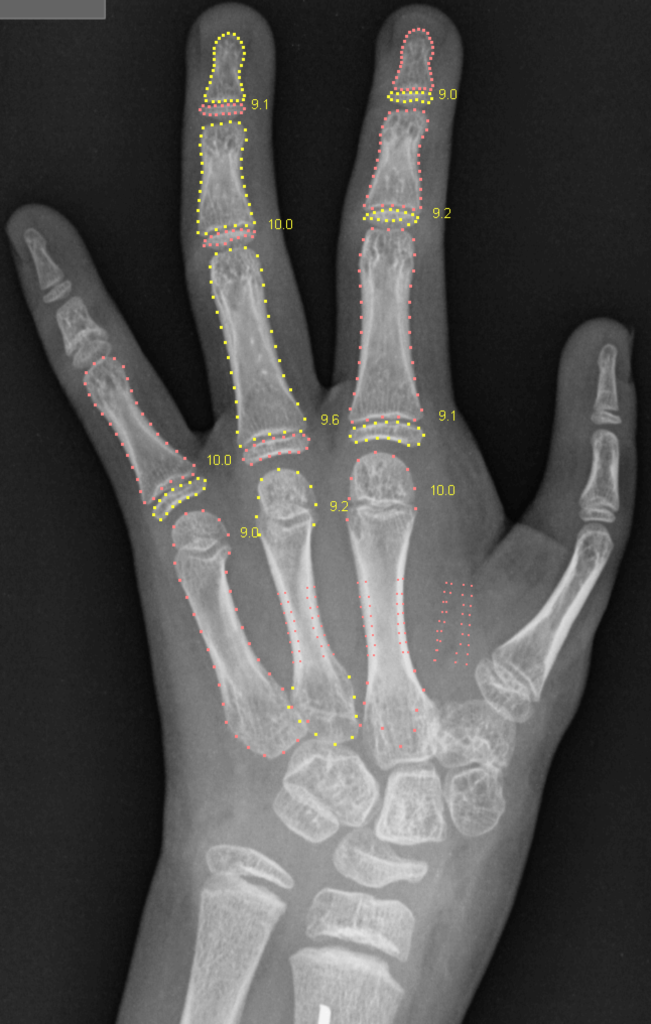

The new paper published by Scientific Reports focuses on this important aspect. It describes how BoneXpert’s self-validation mechanism was designed to not only validate the image as a whole but also to validate that each bone is properly recognised. BoneXpert gives visual feedback on the analysis of each bone, making the validation transparent, or “explained”. BoneXpert rejects only 0.4% of valid hand X-rays, and its accuracy (0.33 y) is far better than the human accuracy (0.58 y), and the system makes 12 times fewer significant errors (>1.5 y) than a human rater, showing that the self-validation effectively curbs the tail of the error distribution.

To illustrate BoneXpert’s bone-by-bone self-validation, consider this girl (RSNA image 4210). She underwent surgery to move the index finger to the thumb position because her own thumb was absent or not functional. The second metacarpal was removed in the process.

BoneXpert refused to recognise the thumb, because its bones do not agree with BoneXpert’s internal model (i.e. BoneXpert’s knowledge) of the thumb.

(Technically this is a pollicised index finger, see https://en.wikipedia.org/wiki/Pollicization. Pollicis is genitive of pollex meaning thumb)

A typical deep learning method would only report an overall bone age without any details, and the doctor would doubt that the AI has sufficient understanding of this image.